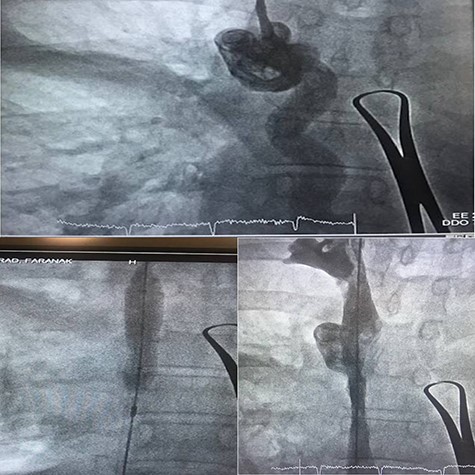

Case 2—a 60-year-old woman with breast cancer underwent a left mastectomy and an implantable chemotherapy port was inserted via right subclavian vein puncture, with fixation of the reservoir in the right thorax. She used her port for 12 months and was referred by an oncologist to explant the port catheter. The general surgeon missed the catheter when he wanted to separate the reservoir from the catheter, and vascular surgery consult was done. Chest radiograph was performed due to suspicion of catheter migration secondary to manipulated breakage of chemo port catheter. It showed that chemo port catheter had migrated from its original location to the right ventricle, traveling across the right atrium. The symptoms related to catheter migration that include palpitations, dyspnea, cough and chest discomfort were absent in this patient, and there was no electrocardiographic changes.

The right jugular vein was punctured, and a 6-Fr sheath was inserted. We removed the catheter from the right jugular vein. No major complication occurred during and after the procedure, and therefore, the patient was discharged on subsequent day (Fig. 3).

To date, the complication rate for the dislodged catheter of a chemo port has remained low with a prevalence of 0.4–4% [7]. The mechanism of catheter dislodgement and migration is not clear. Regardless of how, when a dislodged fragment is found on chest X-ray, early removal as soon as possible is important due to two reasons, one is to stop its distal embolization, which makes retrieval harder, and one more reason is that foreign bodies can cause septicemia, lung abscess, multiple pulmonary emboli, arrhythmias, cardiac wall necrosis resulting in perforation and sudden cardiac death [8]. Percutaneous endovascular retrieval has become a typical technique for foreign body removal. Now it’s a preferred method with a high success rate of 71–100% [2]. In our case, we used the snare technique for retrieval of the migrated catheter without vascular or cardiac complication. So every catheterization lab should have enough expertise to retrieve the migrated catheters albeit the patient is asymptomatic.